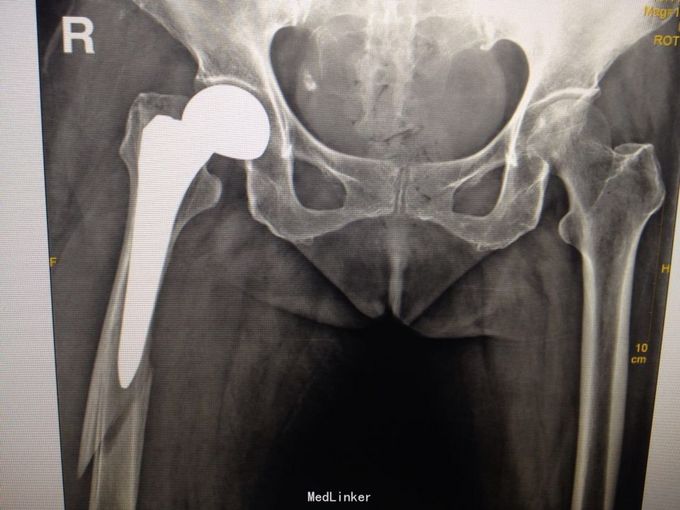

患者84岁女性,4周前因右股骨颈骨折行人工股骨头置换术,术顺,恢复佳,4天前摔倒,致右大腿肿痛,立行不能

右髋部手术瘢痕,无破皮出血及骨质外露,右股骨中段压痛,右股骨纵向叩痛阳性,末端血运感觉好。 X线提示右股骨中段骨折,上段见人工股骨头置换术后,

右股骨头置换术后股骨假体周围骨折(B3) 行右人工股骨头置换术后假体周围骨折切开复位记忆合金钢板+钛缆绑带固定术